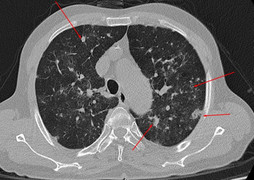

Đây là một vấn đề ảnh hưởng của tim và phổi, xảy ra khi mức độ bão hòa oxy trong máu giảm xuống dưới 85%. Mặc dù có rất nhiều nguyên nhân khiến chân của bạn đổi màu như vậy, nhưng một số nguyên nhân phổ biến nhất đều liên quan đến phổi. Chúng bao gồm bệnh phổi tắc nghẽn mãn tính, tăng áp phổi, hen suyễn và viêm phổi.